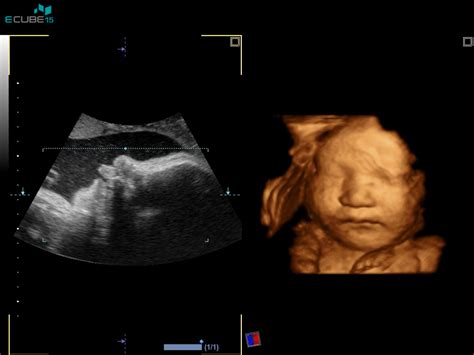

Prvo trimesečje nosečnosti je ključno obdobje za razvoj ploda, ko se izoblikujejo vsi vitalni organi. V tem občutljivem obdobju lahko škodljive snovi iz cigaretnega dima povzročijo nepopravljivo škodo, ki lahko traja vse življenje. Številne raziskave in strokovna mnenja poudarjajo, da je kajenje v nosečnosti, še posebej v prvih treh mesecih, eden najpomembnejših preprečljivih vzrokov neugodnih izidov nosečnosti tako za mater kot za otroka.

V prvem trimesečju nosečnosti poteka intenziven razvoj in izoblikovanje vseh organov ploda. V tem času so celice še posebej občutljive na zunanje dejavnike. Škodljive snovi iz cigaretnega dima lahko povzročijo strukturne nepravilnosti, ki se lahko kažejo kot prirojene napake, kot so zajčja ustnica ali razcep neba. V nekaterih primerih, predvsem ob uporabi prepovedanih drog, pa lahko prihaja tudi do telesnih, nevroloških in duševnih anomalij, ki so doživljenjske in jih ni mogoče odpraviti.